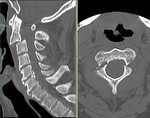

[画像診断]軸椎関節突起間骨折(ハングマン骨折)について 2011-02-01